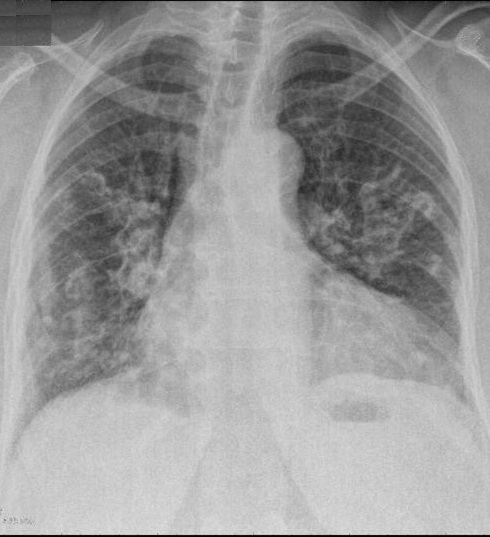

Image

radiolologique cliche de face PA d'une epaissisement

pleural diffuse du poumon droit par consequence de

tuberculose du poumon droit . Aspect radiologique

est opacite en plaque de tres densite s'étend et

recouvre tout le poumon droit , Poumon droit en

fibrose restrictive |